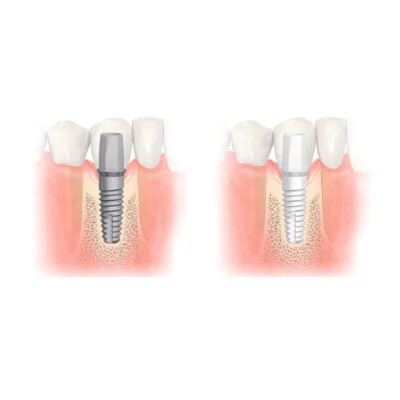

2. ผ่าตัดฝังรากฟันเทียมแบบ Digital Guided Surgery

- ทันตแพทย์จะให้ยาชาเฉพาะที่ และวาง Surgical Guide ที่ออกแบบมาโดยเฉพาะลงบนเหงือกของคนไข้

- ทำการเจาะรูในกระดูกตามตำแหน่งและองศาที่แม่นยำตามไกด์นำร่อง

- ขั้นตอนนี้ใช้เวลาสั้นกว่าและมีความแม่นยำสูง ทำให้เจ็บน้อย และลดอาการบวมช้ำหลังการผ่าตัดได้ดี

3. พักฟื้นและรอการสมานของกระดูก

- รอให้รากเทียมรวมตัวเข้ากับกระดูกอย่างสมบูรณ์ ซึ่งอาจใช้เวลาหลายสัปดาห์ถึงหลายเดือน

- เมื่อรากเทียมยึดติดกับกระดูกอย่างแน่นหนาแล้ว ทันตแพทย์จะทำการใส่เดือยฟัน (Abutment) และครอบฟัน (Crown) ที่ทำจากวัสดุที่มีสีเหมือนฟันจริง เพื่อให้ได้ผลลัพธ์ที่สวยงามและใช้งานได้ตามปกติ